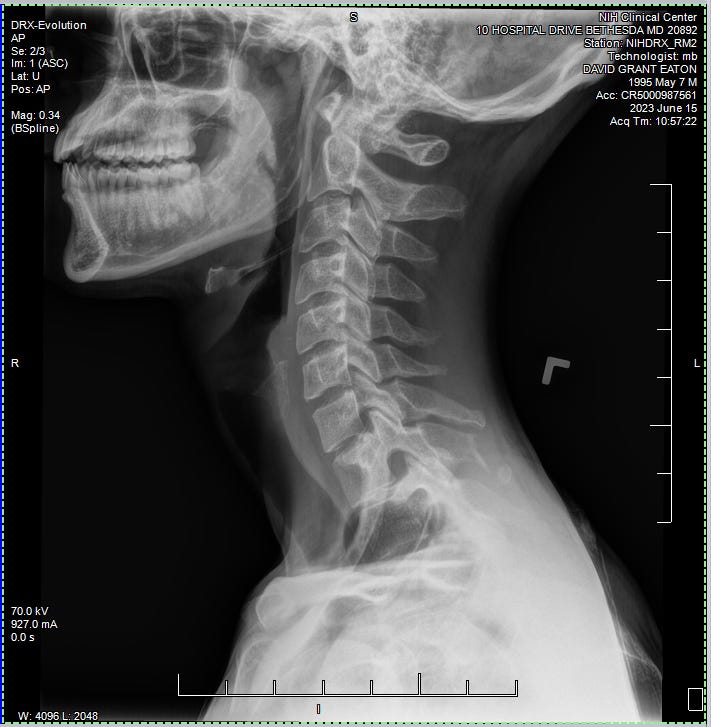

We then headed off of the unit to attend my first rounds of testing. Everywhere I went from this point on required a scan of my wristband, as well as a recitation of my name and date of birth. I did my first ever EKG and Chest X-ray. Zzzzap. I’d never seen such machinery in person before. It was pretty darn cool to see it all in action, and in each of these rooms the operators were super kind and clearly well experienced in their respected fields. I was also surprised that there wasn’t much waiting for these tests. I’m assuming that this study had some kind of priority to move things along rather quickly.

She went ahead and scheduled another X-ray for me, just to be sure there wasn’t any kind of shrapnel left over from the incident. Fortunately none was found, and now I have this sick X-ray as a momento